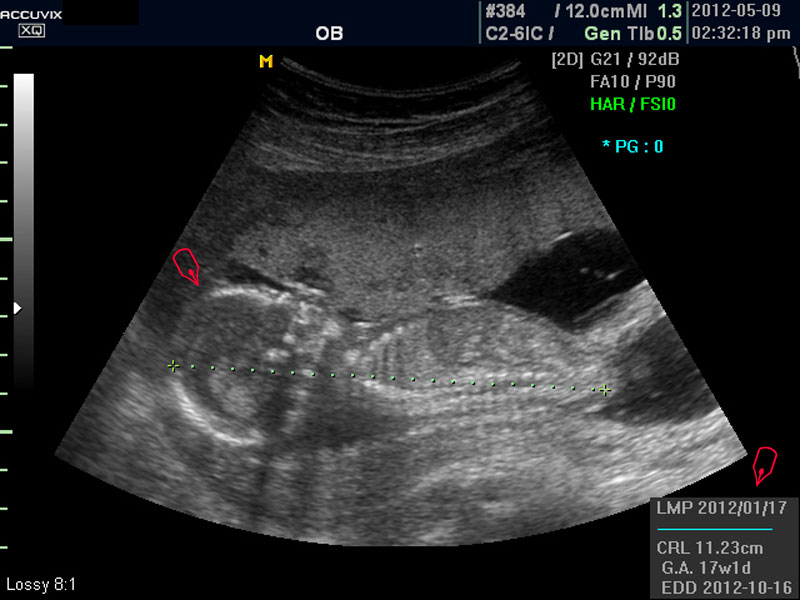

보통 태아의 발육은 머리부터 엉덩이까지의 크기인 CRL(Crown Rump Length의 약자)이 정상인가 하는 것과 태아의 두상 크기인 BPD(BiParietal Diameter의 약자)가 정상 범위에 들어 있는가 하는 것으로 판단합니다.

화면에서 좌측이 태아 머리 부분으로 빨간 펜으로 표시되어 있습니다.

초음파 상 태아의 머리가 좌측인가 우측인가 하는 것은 초음파 탐촉자의 위치를 어디에 두었느냐에 따라 다른 것 뿐으로 화면상 어디 위치하는 지는 중요하지 않습니다.

또한 이 시기는 태아의 크기가 양수에 비하여 아직 작기 때문에 자궁 내에서 하루에도 수십번 이리저리 방향을 바꾸는 시기이기 때문에 위치는 큰 의미가 없습니다.

태아의 머리가 정상 모양인가 크기는 정상인가 하는 것을 살펴 본 후에는 태아의 크기를 측정하고 가슴, 복부, 엉덩이 부분, 상하지 부분이 정상인가 하는 것을 살펴 봅니다.

모든 사진에서 우측 하단에는 기본적인 발육 정보가 기록되는데 세번째 사진에서 빨간 펜으로 표시한 부분이며 그 내용의 의미는 아래와 같습니다.

참고로 이런 측정 수치가 나타나는 양식이나 위치는 초음파 장비마다 다르지만 용어는 대체로 공통된 의학 용어를 사용하기 때문에 대동소이합니다.

1. LMP

Last Menstrual Period의 약자로 최종 월경일입니다. 이런 최종 월경일을 바탕으로 현재의 임신 주수와 초음파상 측정 지표들간에 얼마나 괴리 되어 있나 하는 것을 판단하는 것입니다.

2. CRL

위에 말한 태아 크기를 말하는 지표로 실제 수치가 표시됩니다.

3. GA

Gestational Age의 약자로 우리말로는 임신 주기라고 하며 CRL이나 BPD등을 기준으로 했을때 임신 몇주 며칠에 해당하는 지 나타낸 것입니다.

5.EDD

Estimated Due Date의 약자로 초음파 측정치를 바탕으로 산출한 출산 예정일입니다.